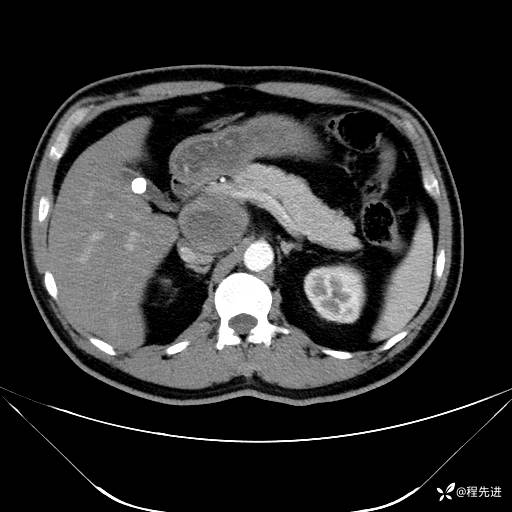

【腹盆】特别精彩病例|发现腹膜后肿物1月余

主诉:发现腹膜后肿物1月余

现病史:患者1月余前查体,行超声检查提示:后腹膜囊实性肿块;慢性胆囊炎伴胆囊内结石;无腹痛腹胀,不伴腹泻发热等;偶感腰背部酸痛。

实验室检查:乙肝表面抗原(+),乙肝e抗体(+),乙肝核心抗体(+)

CT平扫+增强: